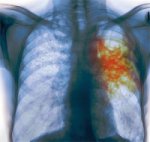

Что такое туберкулез одно из самых древних и очень распространенных хронических гранулематозных инфекционных заболеваний, которое имеет определенные фазы развития. С древних времен туберкулез известен как инфекция, которая поражает людей. Клинические проявления данного заболевания были известны Avicenna, Hippocrates, с Galenus. В 1882 году произошло важное научное событие - немецкий ученый Robert